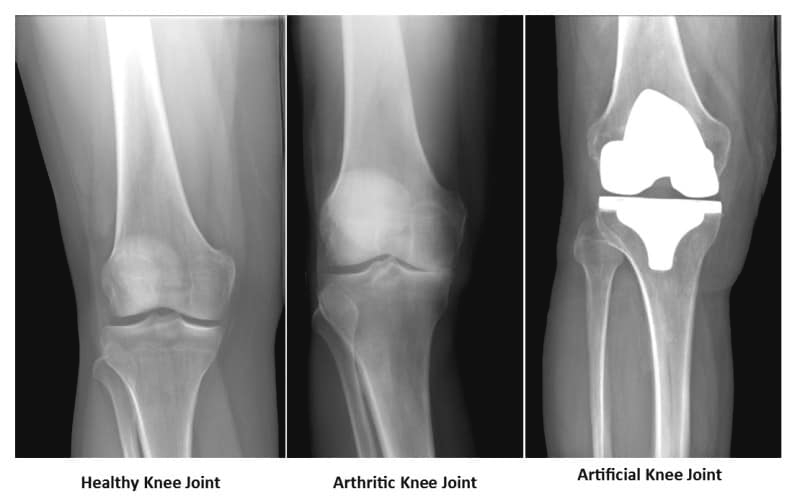

膝關節置換手術,俗稱換骹,是指將嚴重磨損及退化的膝關節部分切除,再換上人工關節。手術通常用於嚴重關節炎患者,通常患者在經過一段時間的保守治療之後,疼痛及功能都不見改善,經骨科醫生評估後,便可考慮進行膝關節換置手術。

膝關節換置手術分為全膝關節置換及半膝關節置換。半膝關節置換恢復時間快,術後的活動限制小,若膝關節只是半側磨損(通常為內側),整體膝關節尚維持正常活動幅度,則可考慮半膝關節置換。而全膝關節置換則是將磨損的股骨及脛骨關節表面切除後,安裝由合金及塑膠組成的人工關節,重建膝關節的功能及活動幅度。現今所採用的人工關節物料非常堅固,置換後膝關節可使用長達15~20年。全膝關節置換術是一項常見且成熟的手術,但仍會有一般手術的併發症,例如感染及靜脈栓塞,提早開始活動有助於避免靜脈血栓的形成。

圖左:健康的膝關節

圖中:已退化的膝關節

圖右:置換後的膝關節